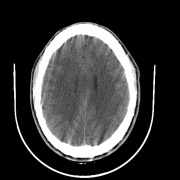

We also include visual examples of consecutive CT slices in Fig. 3. In Scan 1, the baseline Att-MIL produces a wrong prediction at scan level. When using SA, the prediction is correct since dependencies between adjacent slices have been learned. In Scan 2, both models produce correct predictions at scan level, but SA-DMIL is more accurate at slice level. This occurs thanks to the SA loss, that turns the attention scores into smoother values and, therefore, avoids random jumps up and down the decision threshold.

|

| Ground truth | ICH | ICH | Normal | Normal | Normal | ICH | ||

| Att-MIL () [15] | Normal | ICH | ICH | ICH | Normal | ICH | ||

| SA-DMIL- () | ICH | ICH | Normal | Normal | Normal | ICH |